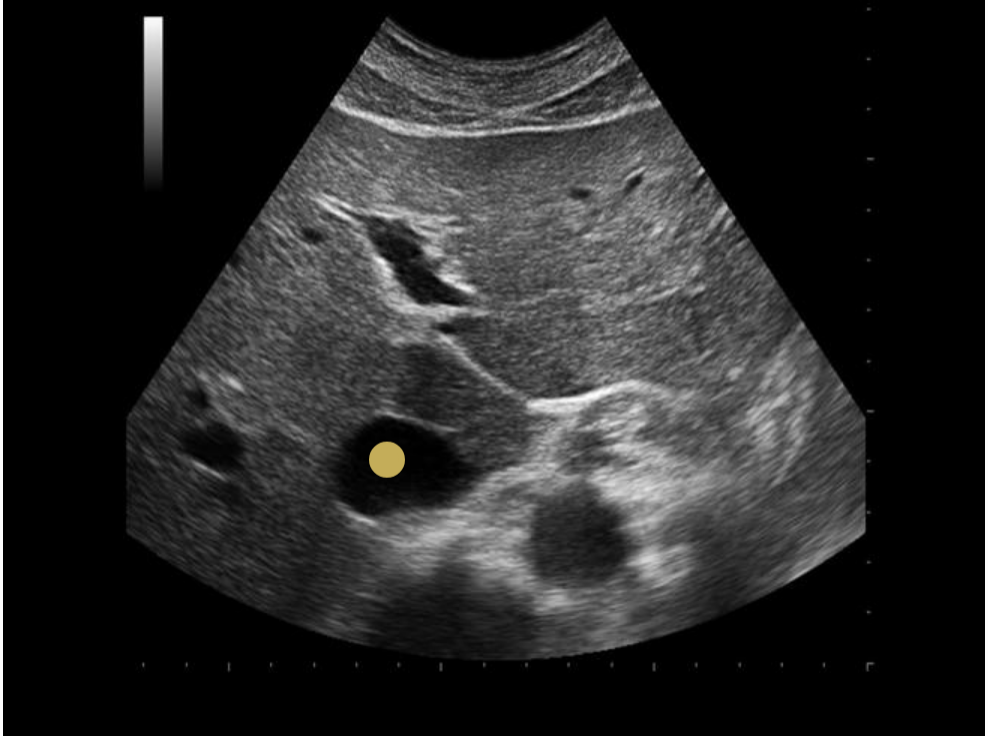

what is the proper caliper placement for assessing portal vein diameter

.

a) inner to inner wall at the junction of splenic vein + portal vein

b) outer to outer wall at the junction of splenic vein + portal vein

c) outer to outer wall where portal vein crosses IVC

d) inner to inner wall where portal vein crosses IVC

d. inner to inner wall where portal vein crosses IVC